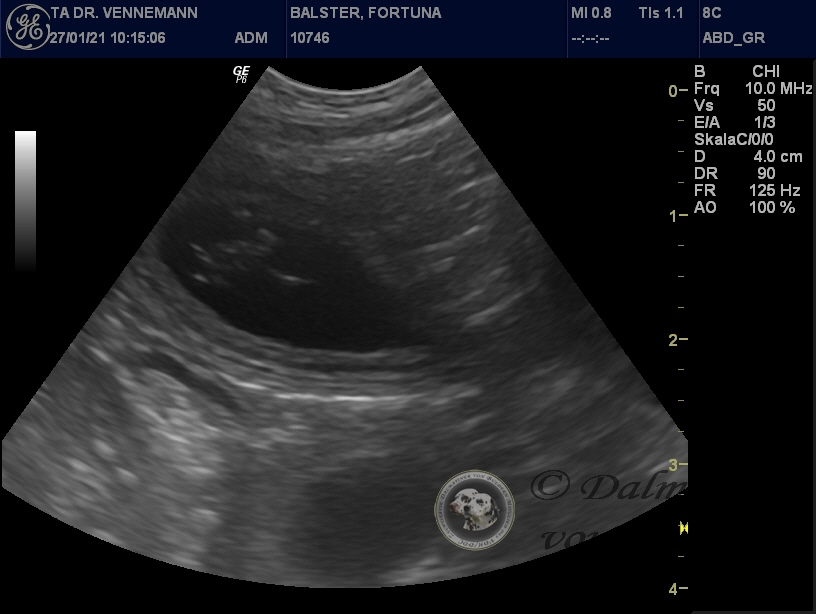

Der Ultraschall beim Tierarzt unseres Vertrauens hat uns Einblick in Selmas Bäuchlein gegeben. Deutlich sichtbar waren die schlagenden Herzchen der Winzlinge zu erkennen - immer wieder ein wunderbarer Anblick!